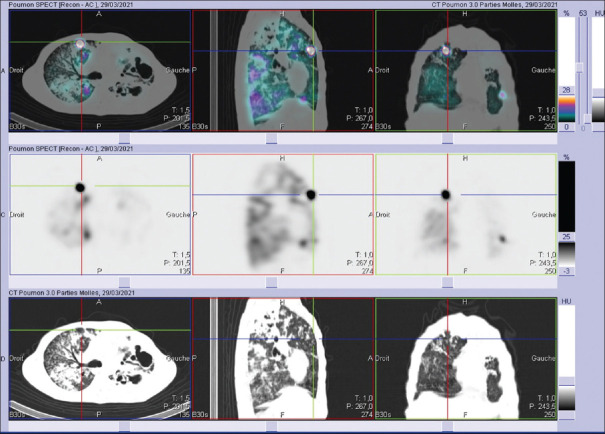

Elaborazione SPECT/CT e quantificazione automatica

I moderni software di elaborazione permettono la fusione delle immagini funzionali (SPECT) con quelle anatomiche (CT). Algoritmi di segmentazione automatica, come quelli basati su intelligenza artificiale (ad esempio AutoLung3D), sono in grado di delimitare i lobi polmonari sulla base della CT e calcolare automaticamente la ripartizione percentuale della ventilazione e della perfusione per ogni singolo lobo.12 Questo approccio riduce la variabilità inter-osservatore associata ai metodi di quantificazione planare manuale.